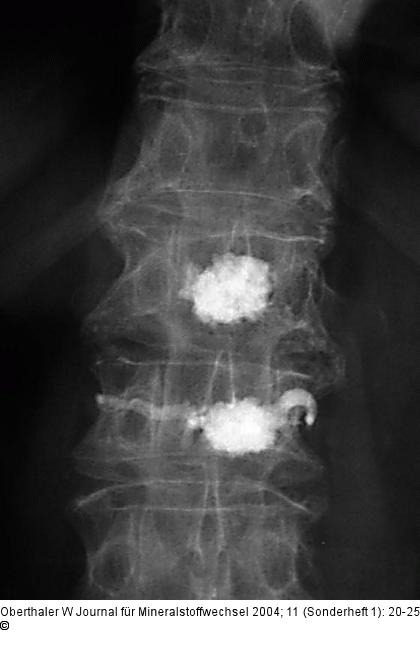

Abbildung 12: Kyphoplastie

Zu flüssiger Zement, daher Austritt in das Venensystem |